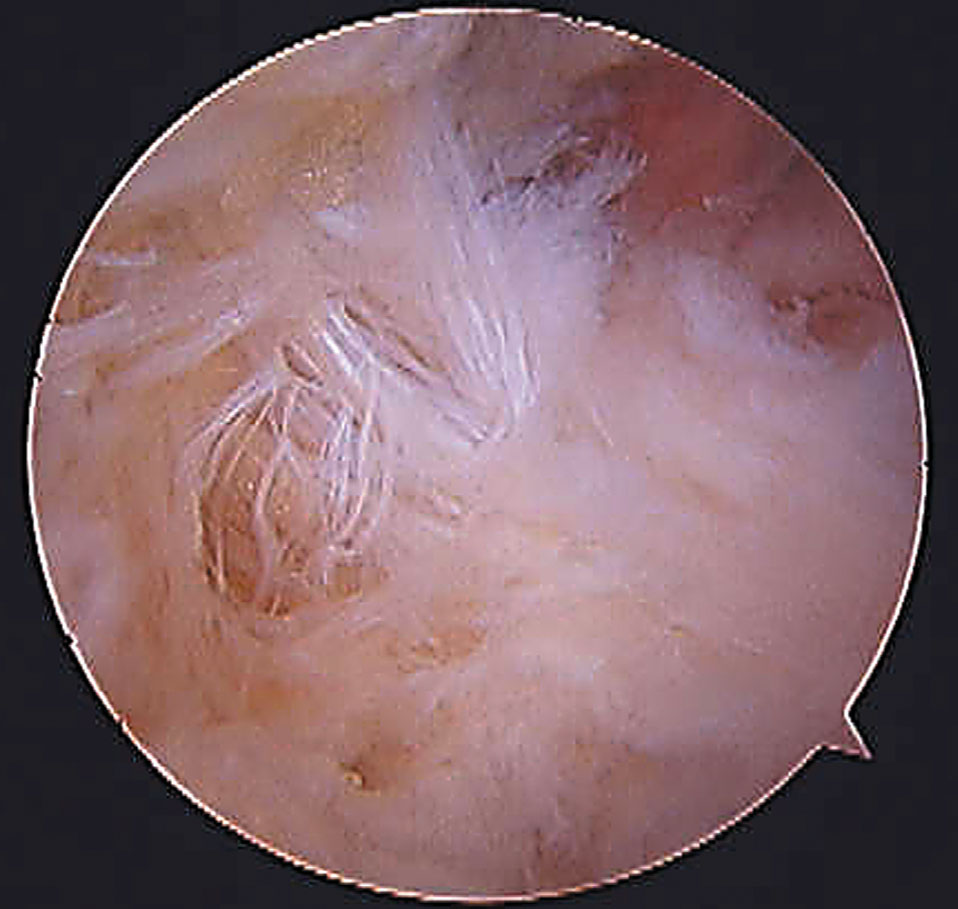

Figura 2: Vista artroscópica del ligamento fibulotalocalcáneo

Si empezamos de atrás para adelante después de la piel y el tejido celular subcutáneo nos encontramos con fibras profundas de la fascia crural, que Rouviére y Canela llamaron ligamento fibulotalocalcáneo (Fig. 2).